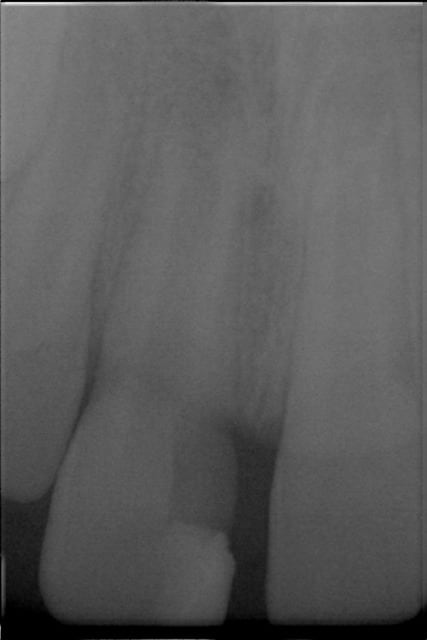

J'ai besoin de conseils pour la prise en charge d'un trauma sur 21 (la radio est inversée) chez un petit garçon de 8 ans.

A la radiographie, l'image est peut être asymétrique entre 11 et 21 : la dent fracturée me semble avoir un canal plus large et un apex plus ouvert.